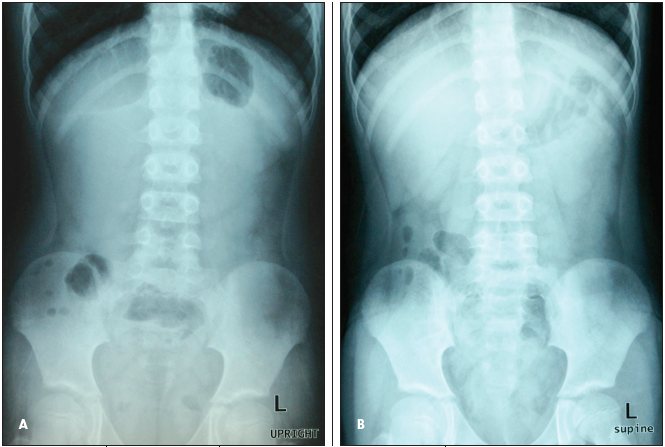

An 8-year-old Hispanic child with no significant medical history presented to our pediatric clinic after 2 episodes of vomiting, diarrhea, and abdominal pain.

Paul Trombley, MD